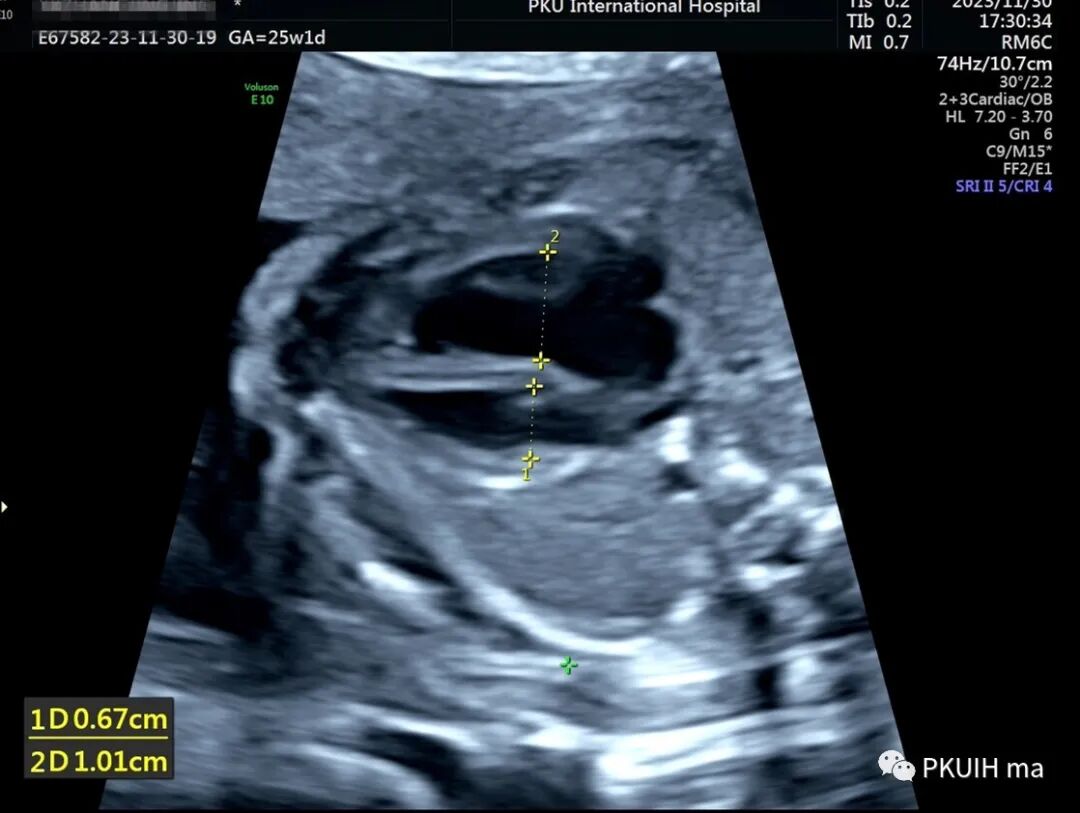

再次可以通过主动脉弓长轴、三血管气管切面观察,主动脉弓长轴切面显示主动脉横弓细窄。主动脉峡部内径与动脉导管内径比值减小与CoA高度相关,峡部与动脉导管内径比≤0.74时发生CoA风险明显增高。同时主动脉弓上的分支血管间距离增大,颈动脉与左锁骨下动脉之间的距离越远,缩窄的可能性就越大。上图CoA主动脉弓长轴切面显示主动脉峡部细窄(AAo:升主动脉,DAo:降主动脉,Ao Arch:主动脉弓,箭头所示为缩窄部位)上图 CoA胎儿三血管气管切面,图像显示主动脉峡部明显细窄,内径1.0 mm (Duct:动脉导管;Isthmus:主动脉峡部)